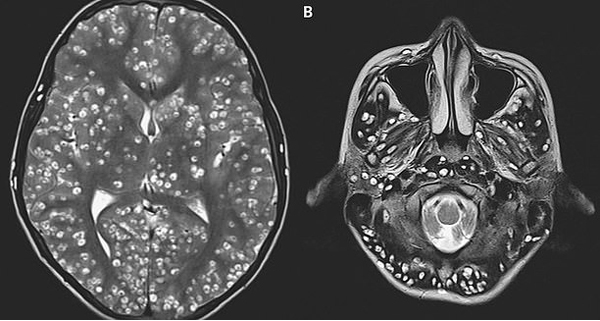

Sau 2 tuần điều trị, bác sĩ vẫn không thể cứu được nam thanh niên do ấu trùng sán lợn đã xâm chiếm toàn bộ não.